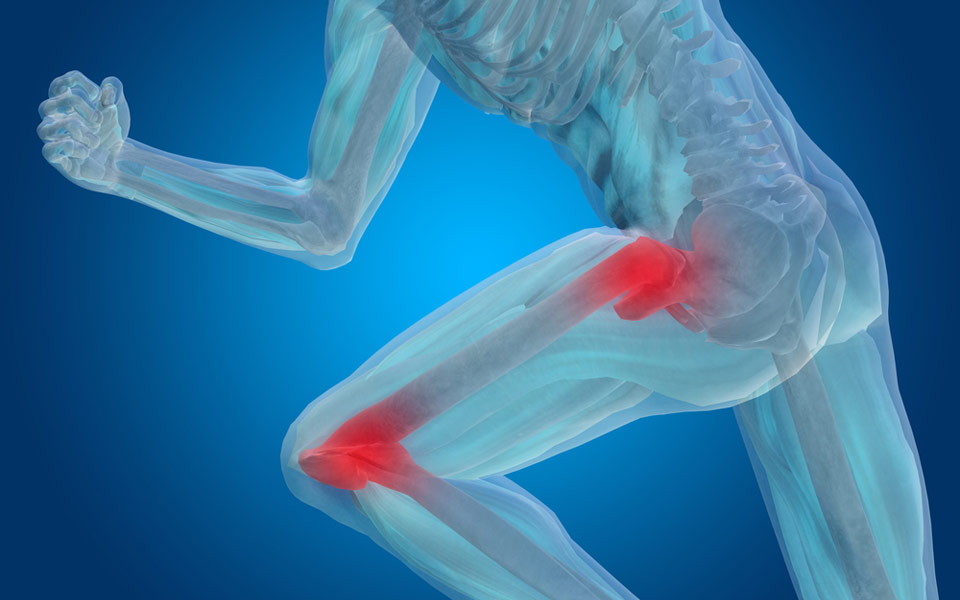

Ολική Αρθροπλαστική Ισχίου-Γόνατος με Προσπελάσεις Ελάχιστης Επεμβατικότητας

Οι αρθρώσεις του ισχίου και του γόνατος είναι οι μεγαλύτερες αρθρώσεις του ανθρωπίνου σώματος. Σκοπό έχουν τη μεταφορά του σώματος προς διάφορες κατευθύνσεις και τη στήριξη του κορμού. Επειδή είναι έντονα φορτιζόμενες αρθρώσεις, υπόκεινται σε μηχανική καταπόνηση και φθορά.